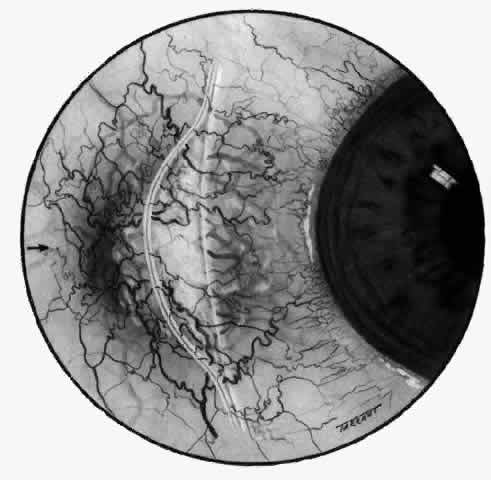

The characteristic features of necrotizing scleritis on fluorescein angiography are hypoperfusion and, eventually, nonperfusion of the vascular networks (Figs. 40 through 43).26 The initial changes are on the venous side of the capillary network; the transit time of the dye increases even if the eye is red and congested. If the disease process persists or has been present for a long time, thrombosis and permanent vaso-occlusive changes occur. These vessels (or the occluded capillary network) are bypassed by the opening of anastomotic channels. New vessels in a granuloma give rise to deep intrascleral leakage of dye (see Fig. 43). Conjunctival and episcleral involvement by the destructive change is late but is always preceded by vaso-occlusive changes that can sometimes be detected with use of the red-free light on the slit lamp (Figs. 44 and 45).

Fig. 40. Early necrotizing scleritis. There is characteristic yellow discoloration of the sclera underlying the conjunctiva at a point of necrosis. In this instance a small filament of tissue has penetrated the conjunctiva.

Fig. 41. Late stage of fluorescein angiogram adjacent to the site of necrosis in the same patient as in Figure 40. Although the eye is uniformly congested, the area near the necrosis shows vascular shutdown, whereas the rest of the conjunctiva and episclera is normally perfused.

Fig. 42. Late arterial phase of fluorescein angiogram in a patient with necrotizing scleritis. All the vessels except the main trunk and the vessels around the limbal perforating vessels are occluded and remain unperfused throughout the angiogram.

Fig. 43. Late venous phase of angiogram of a patient with necrotizing scleritis showing late deep leakage from vessels on the surface of the sclera and leakage of the capillary network at the limbus and the vessels draining it, together with poor or absent perfusion of the remaining vessels.